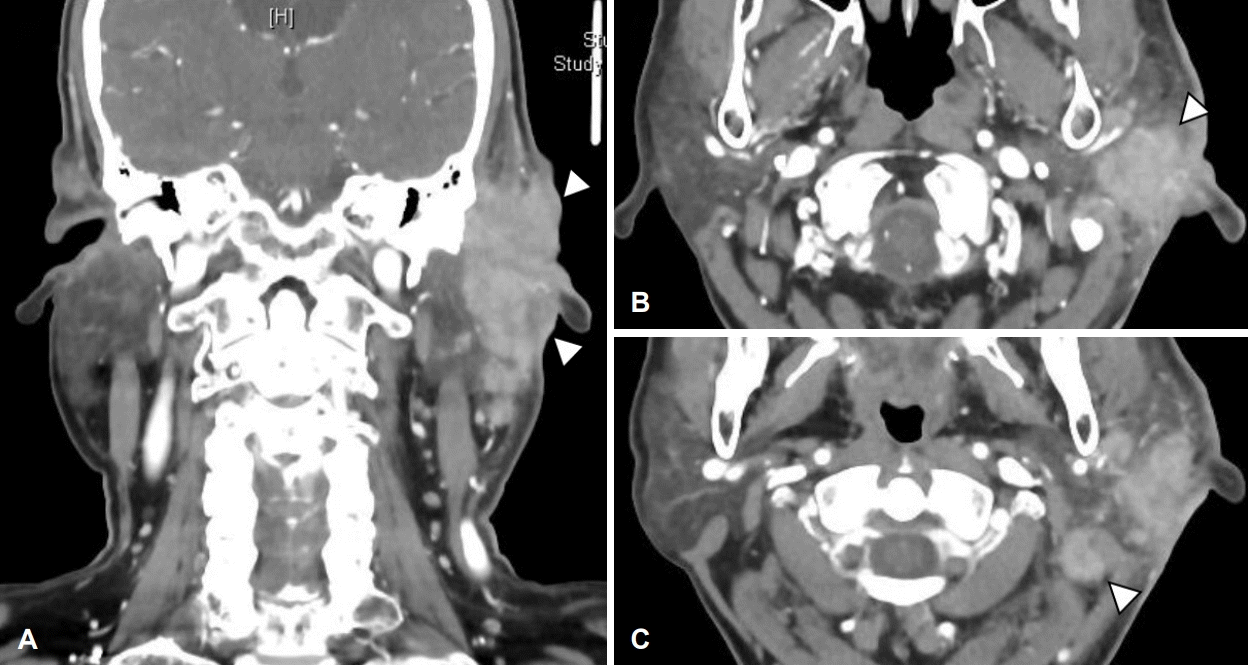

외이도 연조직염 진단하 경험적 경구 항생제 투약 및 병변 부위 드레싱을 1주 이상 시행하였으나, 외이도 부종 악화로 인한 외이도 연골부 협착 소견 및 장액 혈성 이루가 관찰되었다. 이에 치료 시작 후(post start of treatment day) 24일에 입원하여 이주 및 외이도의 염증성 조직에 대하여 정맥 항생제 치료 및 악성종양 의심하 조직 생검을 시행하였다(Fig. 2A and B). 경부 컴퓨터단층촬영상 좌측 외이도와 이개 주변 3.4×2.3×2.9 cm 크기의 병변과 이하선 하부로 타원형의 림프절 비대가 관찰되었다(Fig. 3). 조직 생검상 급성 및 만성 염증소견이 보고되었으며, 균 배양 검사 결과 메티실린 내성 황색포도상구균이 동정되어 vancomycin을 사용하며 보존적 치료를 시행하였다. 치료 초기에는 호전 양상을 보였으나 이후 다시 악화되는 양상이었다(Fig. 2C and D). 백혈구수치, 적혈구침강속도, C-반응성 단백질, 항핵항제, 류마티스 인자, IgG 등의 혈청검사상 정상 범위였으며, 단순 포진 바이러스 및 대상포진 바이러스에 대한 viral marker 검사에서 현성감염증 등의 특이소견은 보이지 않았다.

CT of neck. 3.4×2.3×2.9 cm sized enhancing mass-like lesion at left external auditory canal and left ear auricle with enlarged lymph nodes at periparotid region. A: Coronal view. B: Axial view. C: Axial view of enlarged lymph node.